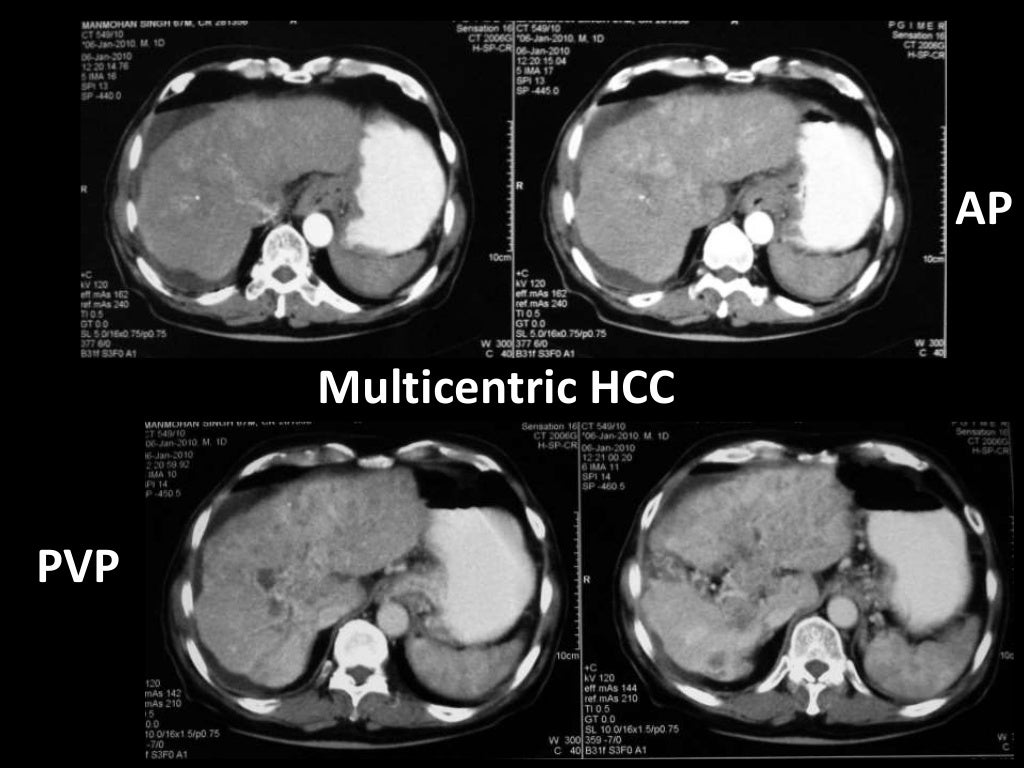

Imaging of Malignant Liver Lesions Malignant Medical Imaging Definition Imaging forms an essential part of cancer clinical protocols and is able to furnish morphological, structural, metabolic and. In contrast, tumors that stay localized and don't spread are called benign. A neoplasm is an abnormal growth of tissue that can be benign (noncancerous) or malignant (cancerous). A malignant tumor is a group of diseased cells defined by one of three. Malignant Medical Imaging Definition.

From www.slideshare.net

Imaging of Malignant Liver Lesions Malignant Medical Imaging Definition A malignant tumor is a group of diseased cells defined by one of three characteristics: Doctors use imaging tests to take pictures of the inside of your body. Benign tumors (noncancerous neoplasms) usually grow. In contrast, tumors that stay localized and don't spread are called benign. Radiologist yolanda bryce (right) and ultrasound supervisor van castor are part of a team. Malignant Medical Imaging Definition.

Imaging of Malignant Liver Lesions Malignant Medical Imaging Definition Imaging is able to spatially map key cancer features and tumor heterogeneity improving tumor diagnosis, characterization, and management. Imaging tests can be used to look for cancer, find out how far it has spread,. Uncontrolled growth, invasion and damage of healthy cells, or metastasizing (spreading) to. Doctors use imaging tests to help find and diagnose. Imaging forms an essential part. Malignant Medical Imaging Definition.